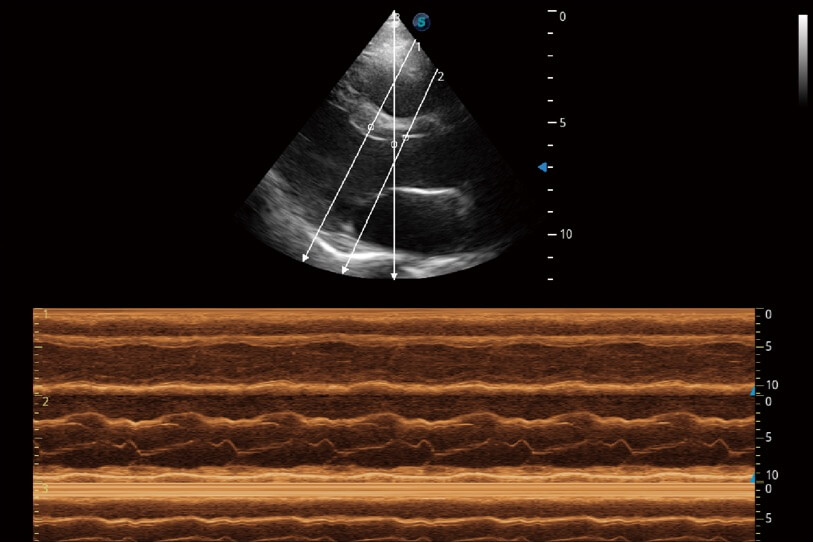

通過360度任意調(diào)節(jié)3條M型取樣線,在同一心動周期上觀察心臟不同位置的運(yùn)動曲線,得到準(zhǔn)確的心功能測量數(shù)據(jù),有效評估心肌運(yùn)動及左心室功能。